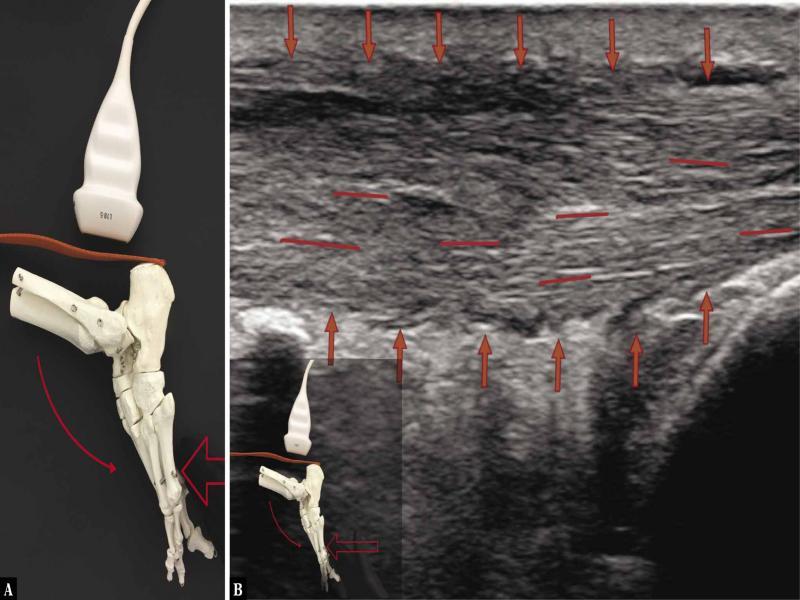

Fig. 5.

![Ultrasound examination protocol. A. The transducer is placed longitudinally above the calcaneal tuberosity, along the AT; active plantar flexion [curved arrow] of the ankle joint with the diagnostician’s hand applying ground-like foot resistance [straight arrow] as in the classical heel-rise test flexion. Evident tension of the AT. The heel-rise movement is made by the force of the triceps surae muscle with the tension of the AT. The image indicates a good function of a surgically treated AT. B. A longitudinal 18–5 MHz US image of the AT; evident fibrillar structure of the tendon fibres [red short lines]; good tendon tension; the image indicates a good function of the AT. [red arrows mark the borders of the tendon]](https://sciendo-parsed.s3.eu-central-1.amazonaws.com/64722e23215d2f6c89dbec00/j_jou.2021.0043_fig_005.jpg?X-Amz-Algorithm=AWS4-HMAC-SHA256&X-Amz-Content-Sha256=UNSIGNED-PAYLOAD&X-Amz-Credential=ASIA6AP2G7AKBY2AOJTK%2F20251216%2Feu-central-1%2Fs3%2Faws4_request&X-Amz-Date=20251216T170210Z&X-Amz-Expires=3600&X-Amz-Security-Token=IQoJb3JpZ2luX2VjEJ%2F%2F%2F%2F%2F%2F%2F%2F%2F%2F%2FwEaDGV1LWNlbnRyYWwtMSJIMEYCIQDpGWJy5nYmL6vQIHHt%2BcL%2F3OSMUmRuP2Jq%2F0ZR1%2FLQBwIhAMOCdMyV4r3yYa%2BF%2FudRVaQIR4fmJylEiwzwqN7lTdT5KrwFCGgQAhoMOTYzMTM0Mjg5OTQwIgz4VpTpHrGQ%2BRwhfVIqmQUmdJgnr7B%2F2TCxvDKqjEoGFRsgxmY1WO7B2uHZlmD80cdU17oWnLhWozEmhOcl3%2FA2q7bDkKBAuPcFO1a7dNHauScY2SzHlX0kIwGWBTyagWuMSXxWSKl7tuRn79BzKKKgACwrvnuaElPejVfsbXCLbokYmV3F5d6L7ZvYrBqtQi69XC21CoAlb8Y6i6%2FgGjbHb96ZBwCqvP7cOXSUTpBBNcWXDb3SBoKgMOvVGHUg3rSkHFBWbeUJWEqFQuQLNZGIPzAiqdGcNpaQoxwYfz5gf2hRAObi1TmBBQCJk0SxpwaFBWoacduWkTQZ5HNbLbV2Y7aFE3mDRSzYCiCfLMQh7Mgepw0nBxMmfE85hi32y%2BHl0YbHclUDfuc6cLW%2FYcTSrFNW5DY1zlMhrYkTdcHwhlV1hhIJTQNjAopybRxyhl8UYT%2FarnBEwsCeDtNSkjr%2BbyoA4Mb304CzPuGRdqK9emQVbV5UYjlPpV4HDHxB%2Feh%2FvM4JIZO4n8g6cp3NqtH4DmY0IW9MSRtklWQp1NGIx%2FvKjGOq7aOzqrJapYKvKLlD5e4RXY6v%2FiOPFbAdlTfn5%2FqC4BWLoxMGssJ9k0H38JHeskVYSwPhVqIo0EtaUeEaKSM06dRorQWA4zp9F2C8ovAo54ubZDzgUdOR0AQTvRjPzuFLiqLDfhn7QV8H0gLPqSM190VJgPIW5IZZPui4U7%2FBneLPSyQBM0j6QtUb8Mst%2FeYnWZLJMIdEPA%2Bv6au%2BzISiEhwEeyP69vVeq%2B5DRurxZDk6yvkPWt7OPS0VcMYYkMEE%2FBKpoOMCHV5smh95YG7YQar4J%2FuRfCRSBakAngbpy9rbUzTx0nincY30w2DOtdkRQ%2B6llm11f5dKO2lDvaYDR9zwsjDY3YXKBjqwAWriJvfX%2BElci0gwZQievDMAbkmHC4QI%2FqxewR1beknZpaCkRtCONkVDPkjy%2BT4qSFomaXZUpQZ4%2FUCmLMIxbgvXVx2C%2F8RvVqLErXggh0KomRU%2B0YjqHSFLW6f4wXhBudqG47DjGNdcJofTT2PytMHHltz%2Fhgs2cVWnTfkhMiVrxvUgXovn9cYHmefQfFeOjU7b7EZJzwNBhn624LDbKUNBrlDn2%2FKsMwkUHsc1t%2Flz&X-Amz-Signature=2aaeba683d1a0ec9b8f452013c52280528da71ec0bc19d68323e1290df9ab0f3&X-Amz-SignedHeaders=host&x-amz-checksum-mode=ENABLED&x-id=GetObject)